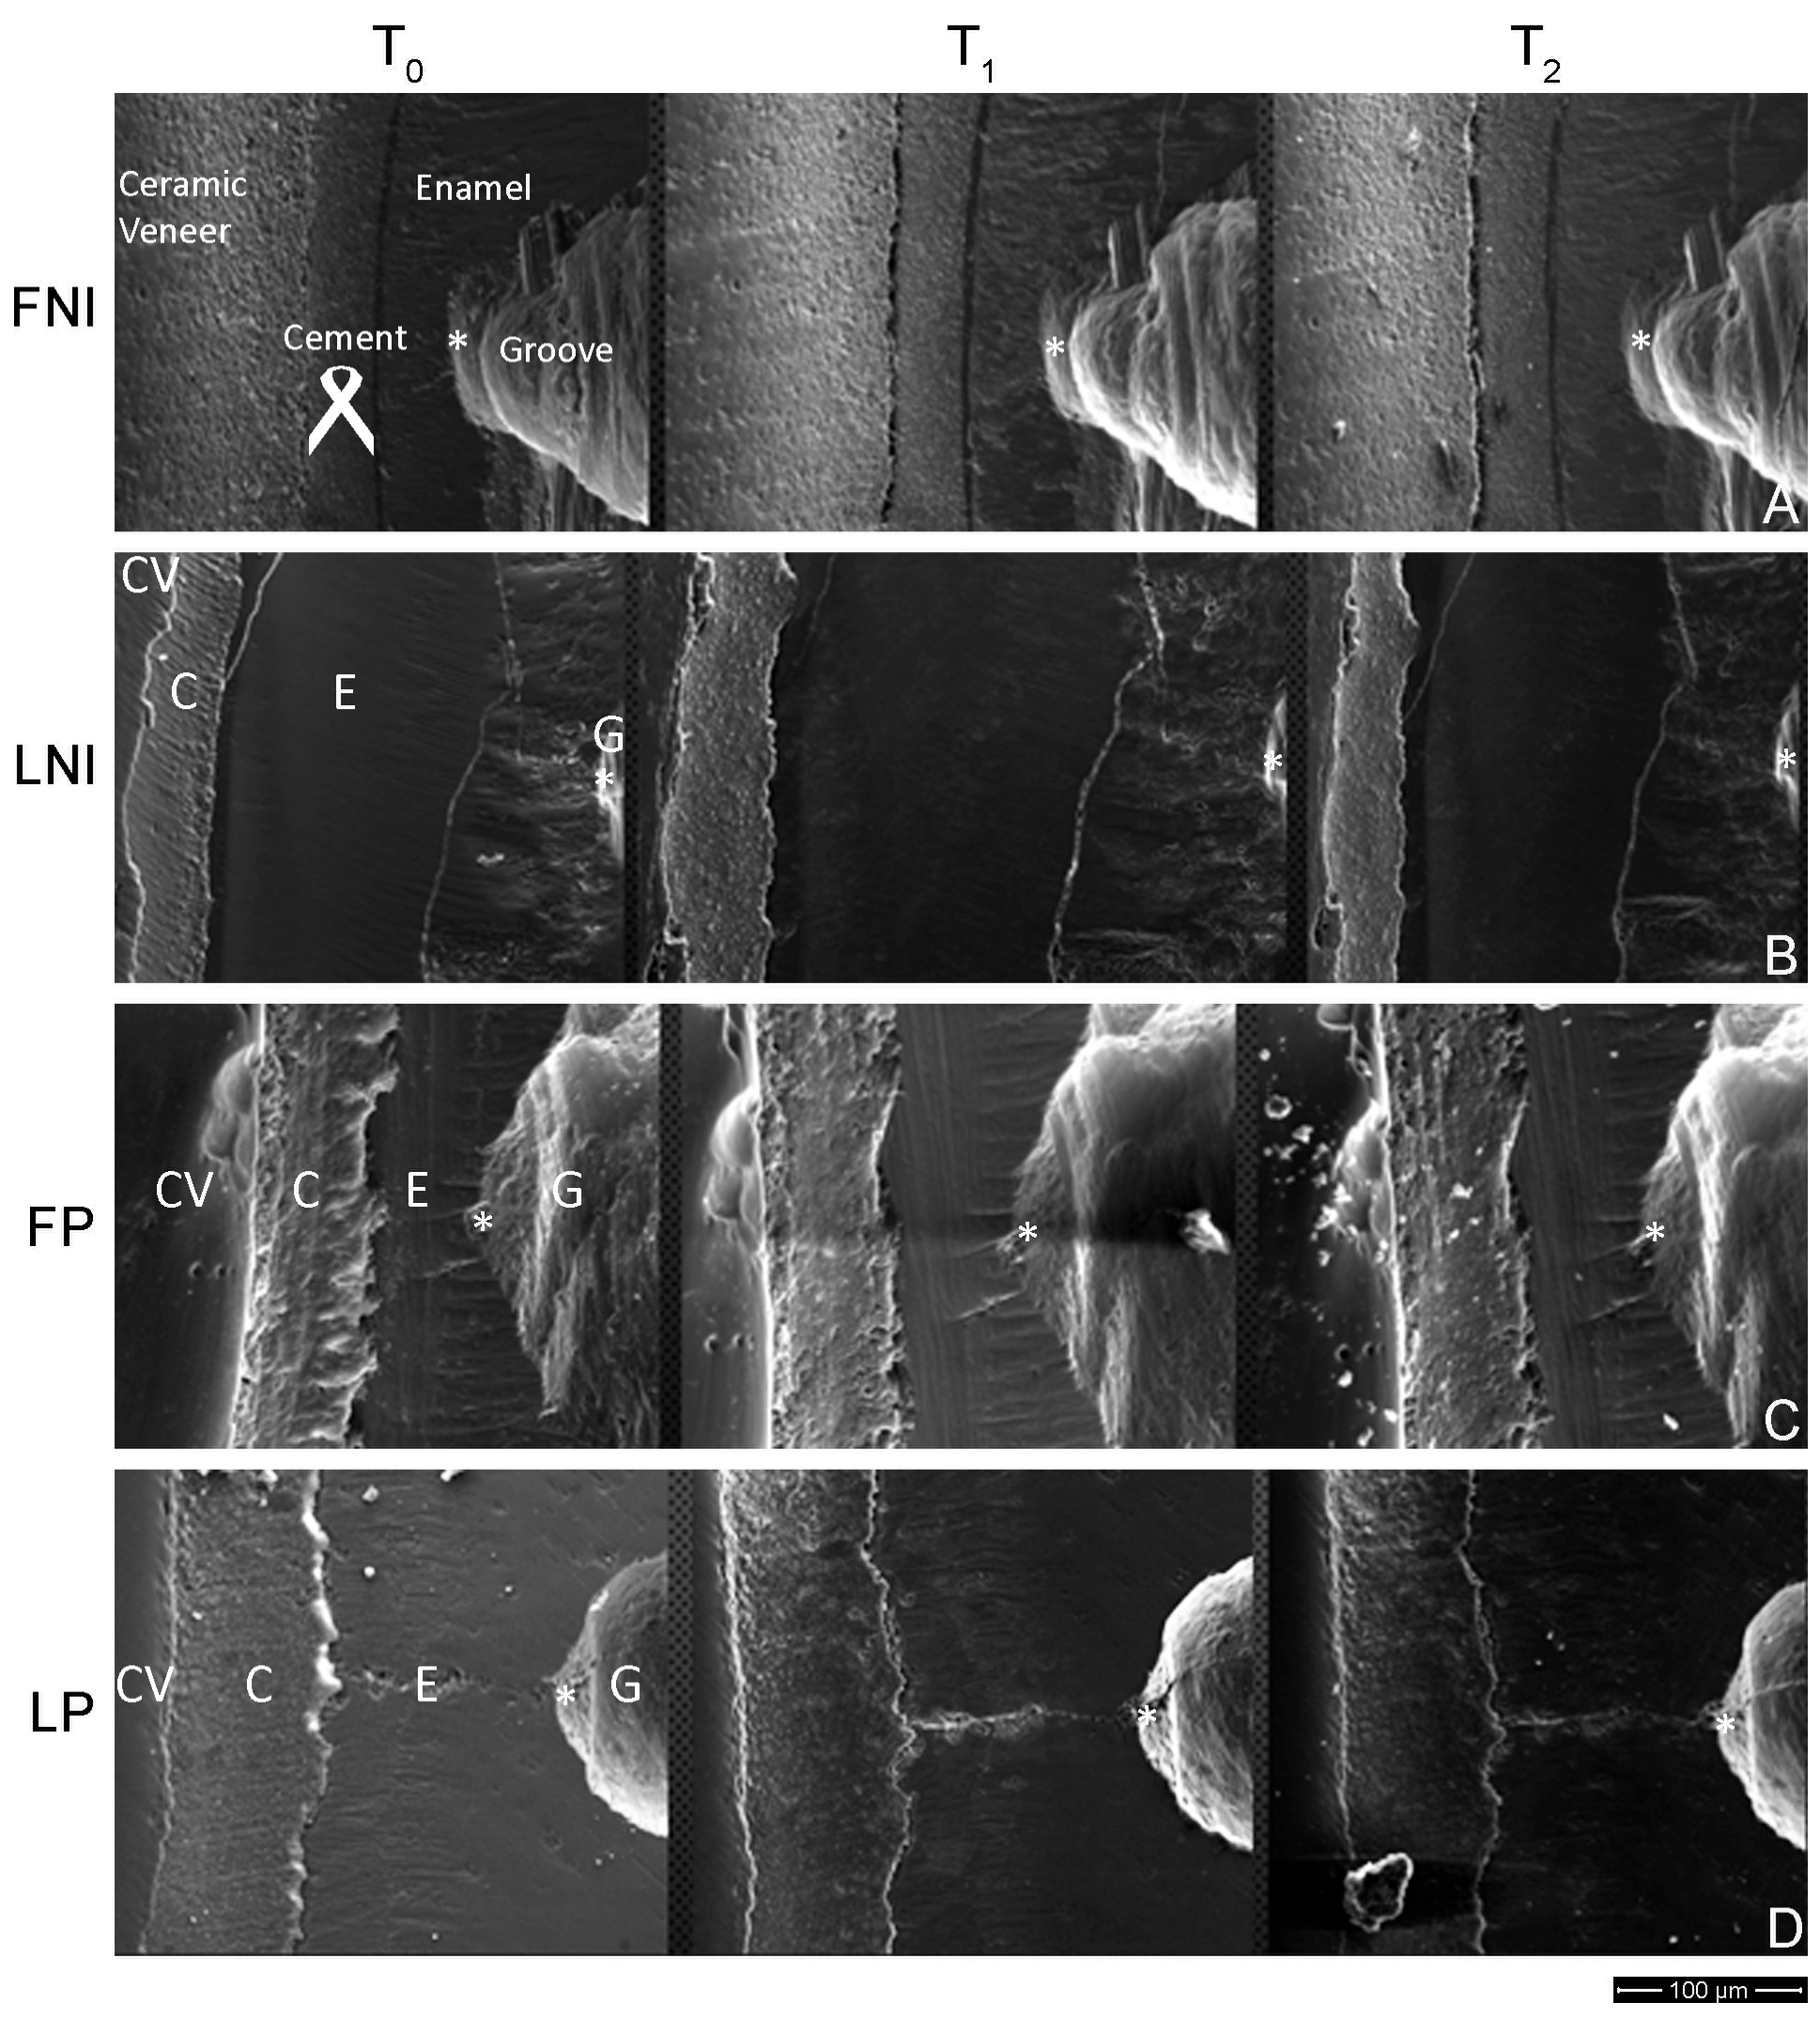

Comparison of the Marginal Integrity of Sectional Non-Invasive Laminate Veneers Versus Sectional Minimally Invasive Laminate Veneers Under Artificial Aging

3. Results